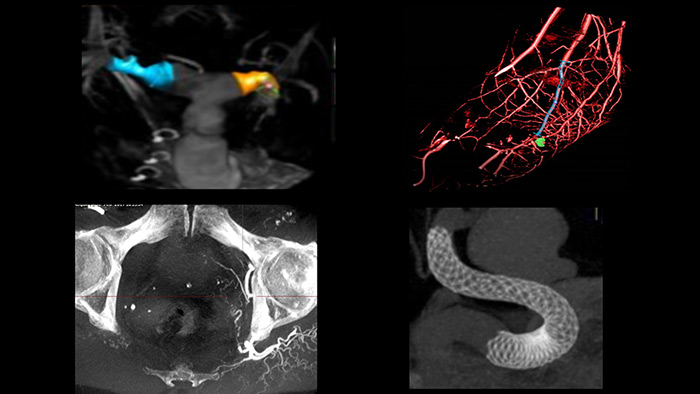

El laboratorio de cateterismo integrado de Azurion ofrece el exclusivo sistema digital IVUS de instalación automática desde la mesa de IntraSight. El estudio ADAPT-DES informó que la orientación del IVUS se asoció con un cambio en la estrategia de PCI el 74 % del tiempo.10-13 Nuestra exclusiva función de Corregistro IVUS4 mapea la anatomía 3D del vaso para la angiografía y crea una imagen superpuesta que puede ayudarle a determinar la magnitud de la lesión, el tamaño de los vasos y la implementación óptima del stent para obtener mejores resultados del tratamiento.10,11,14

SmartCT* le proporciona imágenes similares a las de la TC lo que le permite hacer mediciones y visualizaciones avanzadas en la pantalla táctil en la mesa, para estudiar el tipo y la extensión de la enfermedad con gran detalle. Las imágenes 3D de SmartCT* pueden ayudar a revelar información no aparente en las imágenes 2D o de la DSA. Esta información adicional puede cambiar el diagnóstico, la planificación del tratamiento o la administración del tratamiento, lo que respalda un mejor resultado para el paciente.17-19

Guarde una instantánea de la imagen 3D para consultar fácilmente. Con un solo clic de SmartCT Snapshot puede guardar con facilidad una instantánea de un detalle relevante. La instantánea se muestra en el monitor de referencia de Azurion para que pueda consultarla según sea necesario.